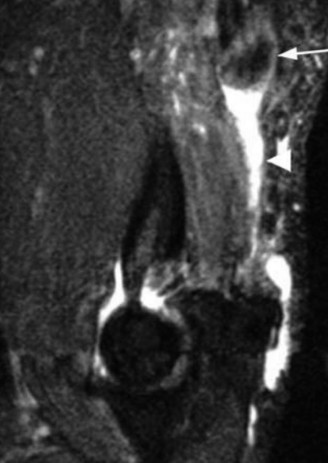

The patient undergoes conservative management consisting of rest, anti-inflammatory medications, and physical therapy. After six months, he is still not able to return to play and has progressively worsening symptoms with attempted throwing. He has a moderate elbow effusion as well as a 20-degree flexion contracture. An elbow MRI arthrogram is obtained and shown (Fig. 2–112). He elects to proceed with elbow arthroscopy. Intraoperative arthroscopic images are shown (Figs. 2–113 and 2–114).

Figure 2–112

The correct answer is (E). Although the diagnosis is most consistent with a distal triceps tendon rupture, this patient has 3/5 motor strength. An MRI must be obtained in this instance to assess the location and degree of tendon involvement (see Fig. 2–123). Physical examination and strength grading can be difficult and inconsistent in the acute setting, even leading to some missed diagnoses. Partial ruptures may present with profound strength deficits, whereas complete ruptures may exhibit little or no strength deficit due to compensation from an intact lateral triceps expansion or the anconeus. This makes an MRI essential for accurate diagnosis and preoperative planning. In general, tears <50% can be managed conservatively with satisfactory results. Partial tears >50% are managed on an individualized basis. They can be managed nonsurgically in sedentary or medically infirm individuals, with repair indicated for active or younger individuals. Complete tears are usually best treated surgically.

Figure 2–123_MRI depiction of retracted triceps tendon (_white arrow) and fluid filled gap (arrowhead).